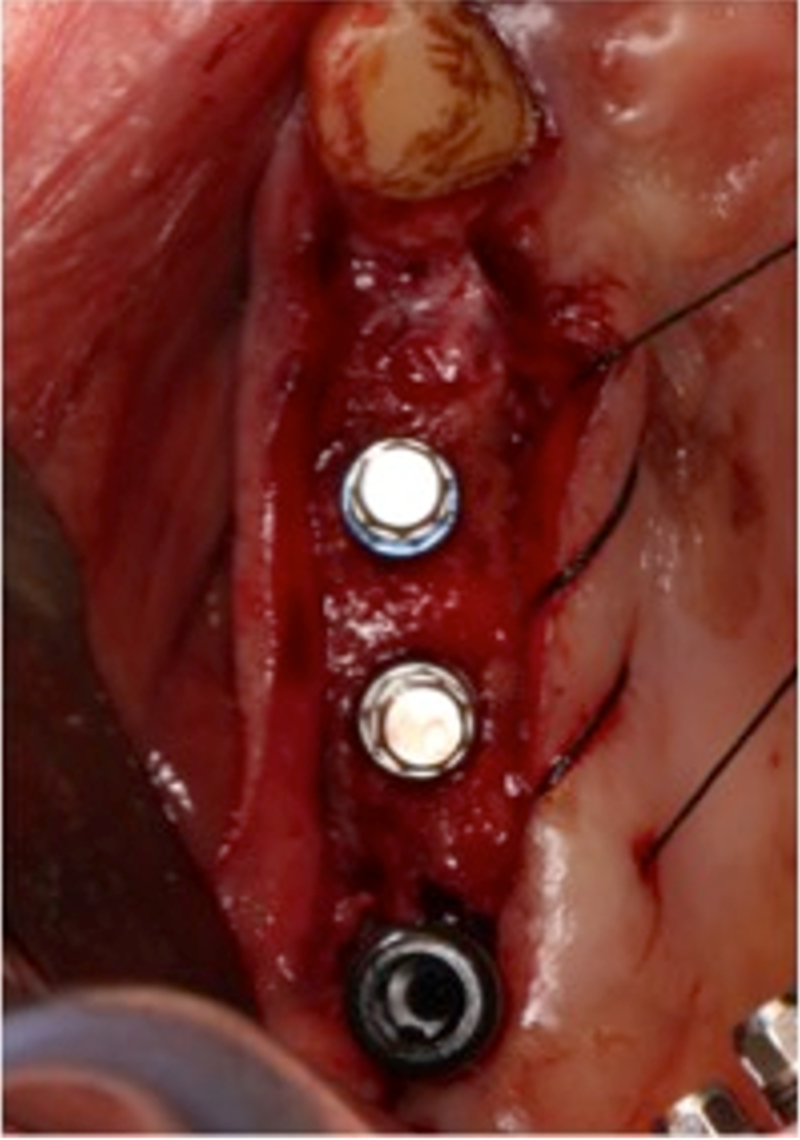

®按照術前方案進行備洞及植體植入

®按照術前方案進行備洞及植體植入,醫(yī)生可以通過屏幕軟件引導對手術中植入點、角度、深度實時追蹤

®對植體深度及方向進行確認

®完成3顆植體的植入,植體位點如術前方案設計,均在同軸線。

®進行縫合